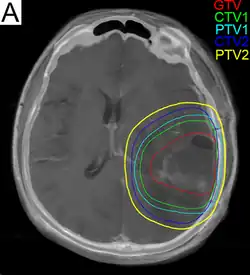

Subsequent to surgery, radiotherapy becomes the mainstay of treatment for people with glioblastoma. It is typically performed along with giving temozolomide.[10] A pivotal clinical trial carried out in the early 1970s showed that among 303 GBM patients randomized to radiation or best medical therapy, those who received radiation had a median survival more than double those who did not.[77] Subsequent clinical research has attempted to build on the backbone of surgery followed by radiation. Whole-brain radiotherapy does not improve when compared to the more precise and targeted three-dimensional conformal radiotherapy.[78] A total radiation dose of 60–65 Gy has been found to be optimal for treatment.[79]